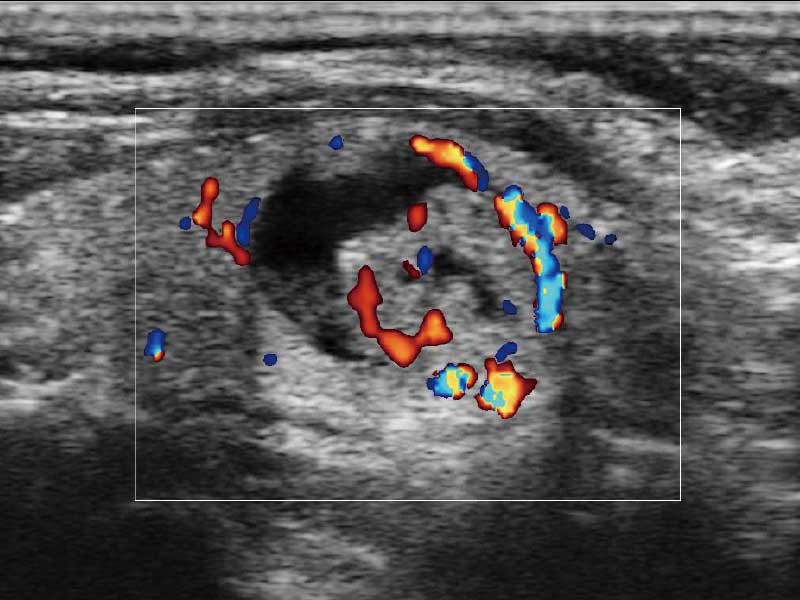

μ-Scan微米成像、空间复合成像、高分辨率血流成像。

PW自动包络分析,对血流动力学指数快速测量,自动生成结果,同时也支持可编辑的手动包络功能,对感兴趣区域进行单独分析,提高诊断准确率。